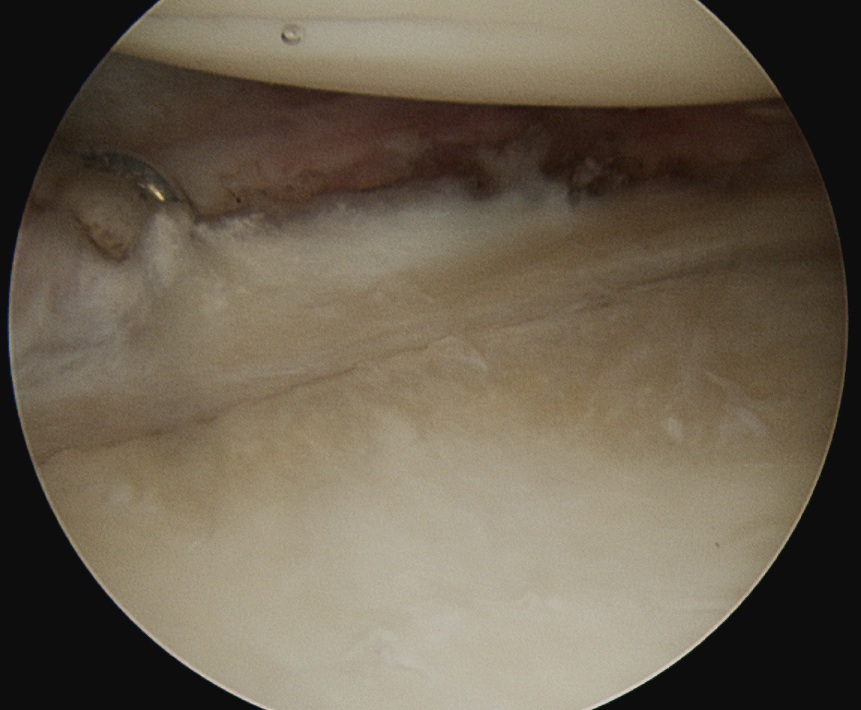

Release posterior IGHL from 9 to 11 o'clock, leaving labrum intact

+/- release inferior capsule, beware injury to axillary nerve

Release posterior IGHL